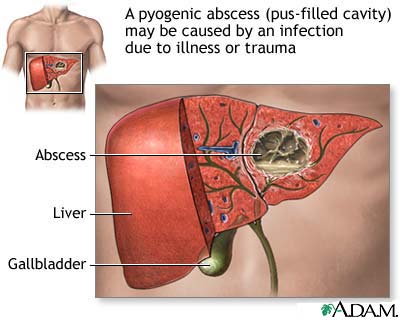

- Pyogenic liver abscess

Abscesses can form in almost any part of the body. The skin, under the skin, and around the teeth are the most common sites. Abscesses may be caused by bacteria, parasites, and foreign substances.

Abscesses in the skin are easy to see. They are red, raised, and painful. Abscesses in other areas of the body may not be seen, but they may cause organ damage.